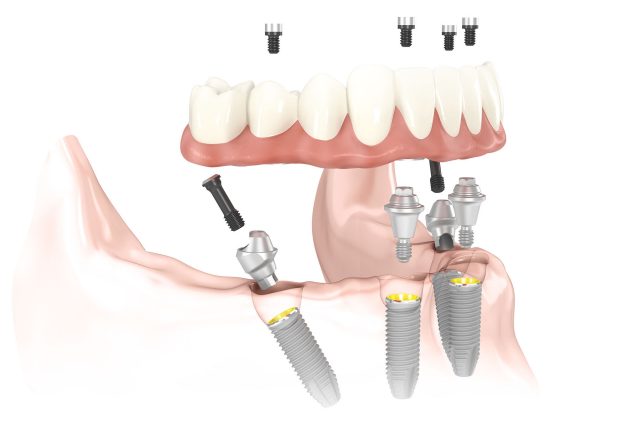

Procedura consta in:

– inserarea a 4 sau 6 (sau 8 in unele cazuri) implanturi/arcada – in functie de lucrarea protetica pe care si-o doreste pacientul.

– lucrare protetica provizorie fixa – care se aplica in urmatoarele 24/48 ore de la interventia chirurgicala;

– lucrare protetica definitiva fixa – care se va realiza dupa 3-6 luni de la inserarea implanturilor. Perioada de osteointegrare este foarte importanta si trebuie respectata cu strictete!

Procedura chirurgicala se realizeaza intr-o singura sedinta (extractii + inserarea implanturilor), urmand ca in urmatoarele 24/48 ore sa se aplice si lucrarea provizorie fixa.

Dupa ce trece perioada de osteointegrare (aproximativ 3-6 luni – functie de maxilar) se va putea realiza lucrarea protetica definitiva fixa.